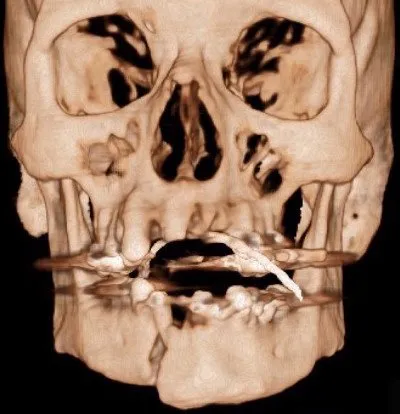

Fratura Pan-faciais

Uma fratura panfacial é uma lesão facial que afeta múltiplas regiões da face, envolvendo o terço superior, médio e inferior. Essa fratura é considerada uma das mais graves e complexas, pois afeta uma grande parte da estrutura facial, incluindo os ossos frontal, nasal, zigomático, maxilar, mandíbula e osso orbital.